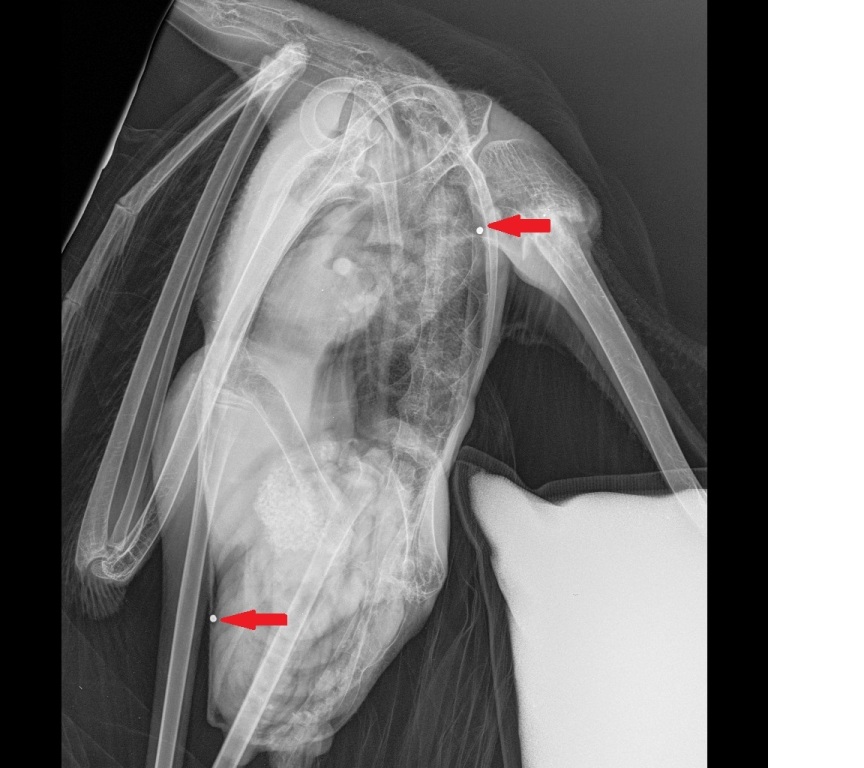

Παράνομο κυνήγι προστατευόμενων ειδών στην περιοχή του Ταμιευτήρα της Κάρλας, καταγγέλλει ο Φορέας Διαχείρισης Κάρλας. Πιο συγκεκριμένα, όπως αναφέρεται σε συγκεκριμένο δελτίο Τύπου, «το Σάββατο 24/12/2016, μετά από επικοινωνία με μέλος της Ελληνικής Ορνιθολογικής Εταιρείας, προσωπικό του Φορέα Διαχείρισης Περιοχής Οικοανάπτυξης Κάρλας – Μαυροβουνίου – Κεφαλόβρυσου – Βελεστίνου πραγματοποίησε αυτοψία κατά τη διάρκεια της οποίας εντόπισε και περισυνέλλεξε, τραυματισμένο νεαρό άτομο φοινικόπτερου – Phoenicopterus roseus, το οποίο απεστάλη για περαιτέρω περίθαλψη στην οργάνωση Δράση για την Άγρια Ζωή στη Θεσσαλονίκη. Όπως διαπιστώθηκε μετά από ακτινολογική εξέταση, το φοινικόπτερο έφερε σκάγια από κυνηγετικό όπλο. Ο περιφραγμένος χώρος του Τεχνητού Υγροτόπου δέχεται μεγάλο αριθμό κυνηγών, παρότι το μεγαλύτερο τμήμα του προστατεύεται από τις διατάξεις του Καταφυγίου Άγριας Ζωής Κάρλας, για το οποίο ισχύει γενική απαγόρευση θήρας. Ο Φορέας Διαχείρισης Π.Ο.Κα.Μα.Κε.Βε. θα προβεί σε όλες τις απαραίτητες νόμιμες ενέργειες έναντι των υπευθύνων παραβατών, οι οποίοι παραβιάζουν κάθε νομικό κείμενο περί προστασίας της άγριας ορνιθοπανίδας και του φυσικού περιβάλλοντος. Ζητά επίσης την συνεργασία με τις αρμόδιες υπηρεσίες για τον συντονισμό δράσεων αποτροπής επιπλέον παρόμοιων περιστατικών. Τέλος, παρακαλούνται οι δημότες του δ. Ρήγα Φεραίου και οι επισκέπτες να καλούν στo τηλ. 2480-73993 όταν αντιλαμβάνονται τέτοιου είδους κινήσεις».